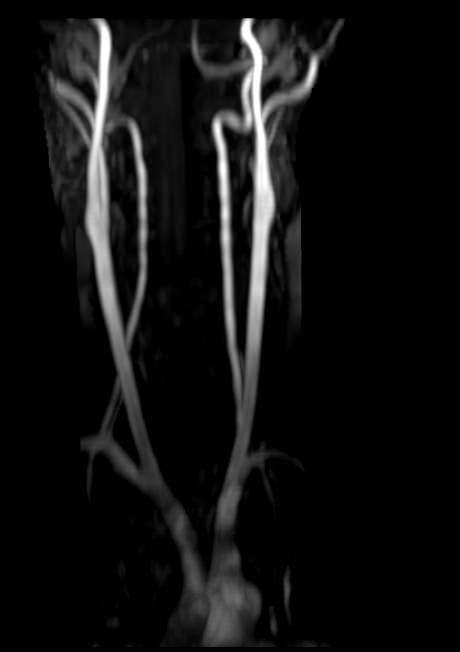

Кроме того, в области шеи проходят крупные кровеносные сосуды, кровоснабжающие все структуры головного мозга и мягких тканей головы. К ним относятся плечеголовной ствол, сонные и позвоночные артерии, которые далее в полости черепа соединяются между собой в Виллизиев круг. Это анатомическое образование позволяет компенсировать мозговой кровоток при патологических состояниях.

• участки сужения, извитость, образование петель и перегибов сосудов;

• нарушения оттока крови за счет тромбообразования в венозном русле;

• ангиомы, сосудистые мальформации;